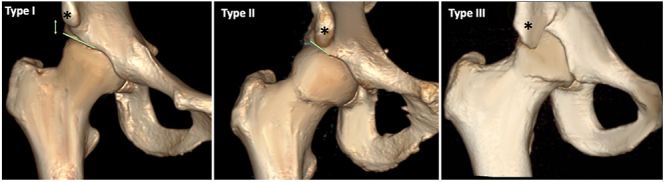

髋关节疼痛可由关节外情况引起,如脊柱下撞击、髂腰肌撞击和坐骨股撞击。这些综合征通常继发于髋关节或腰椎的潜在病变。虽然大多数病例通过活动调节和物理治疗进行保守治疗,但对难治性病例考虑手术干预。计算机断层扫描(CT)和磁共振成像(MRI)等成像对于诊断这些疾病至关重要,因为临床症状可能是非特异性的。CT扫描有助于确定诱发因素,如髋臼形态、股骨变形和髋臼变形,而MRI有助于排除其他情况和检测软组织病理。虽然通常观察到积极的治疗结果,但结果和程序存在差异,并且缺乏长期随访研究。治疗的并发症是一个问题,但大多数报道的并发症是轻微的性质。

Hip pain can be caused by extra-articular conditions such as subspine impingement, iliopsoas impingement, and ischiofemoral impingement. These syndromes are frequently secondary to underlying pathologies involving the hip joint or lumbar spine. While most cases are managed conservatively through activity modification and physiotherapy, surgical intervention is considered for refractory cases. Imaging, such as computed tomography (CT) scans and magnetic resonance imaging (MRI) is crucial for diagnosing these conditions, as clinical symptoms can be nonspecific. CT scans help identify predisposing factors such as acetabular morphology, femoral version, and acetabular version, while MRI is useful for ruling out other conditions and detecting soft tissue pathology. Although positive treatment outcomes are generally observed, there are variations in results and procedures, and long-term follow-up studies are lacking. Complications of the treatments are a concern, but most reported complications are minor in nature.